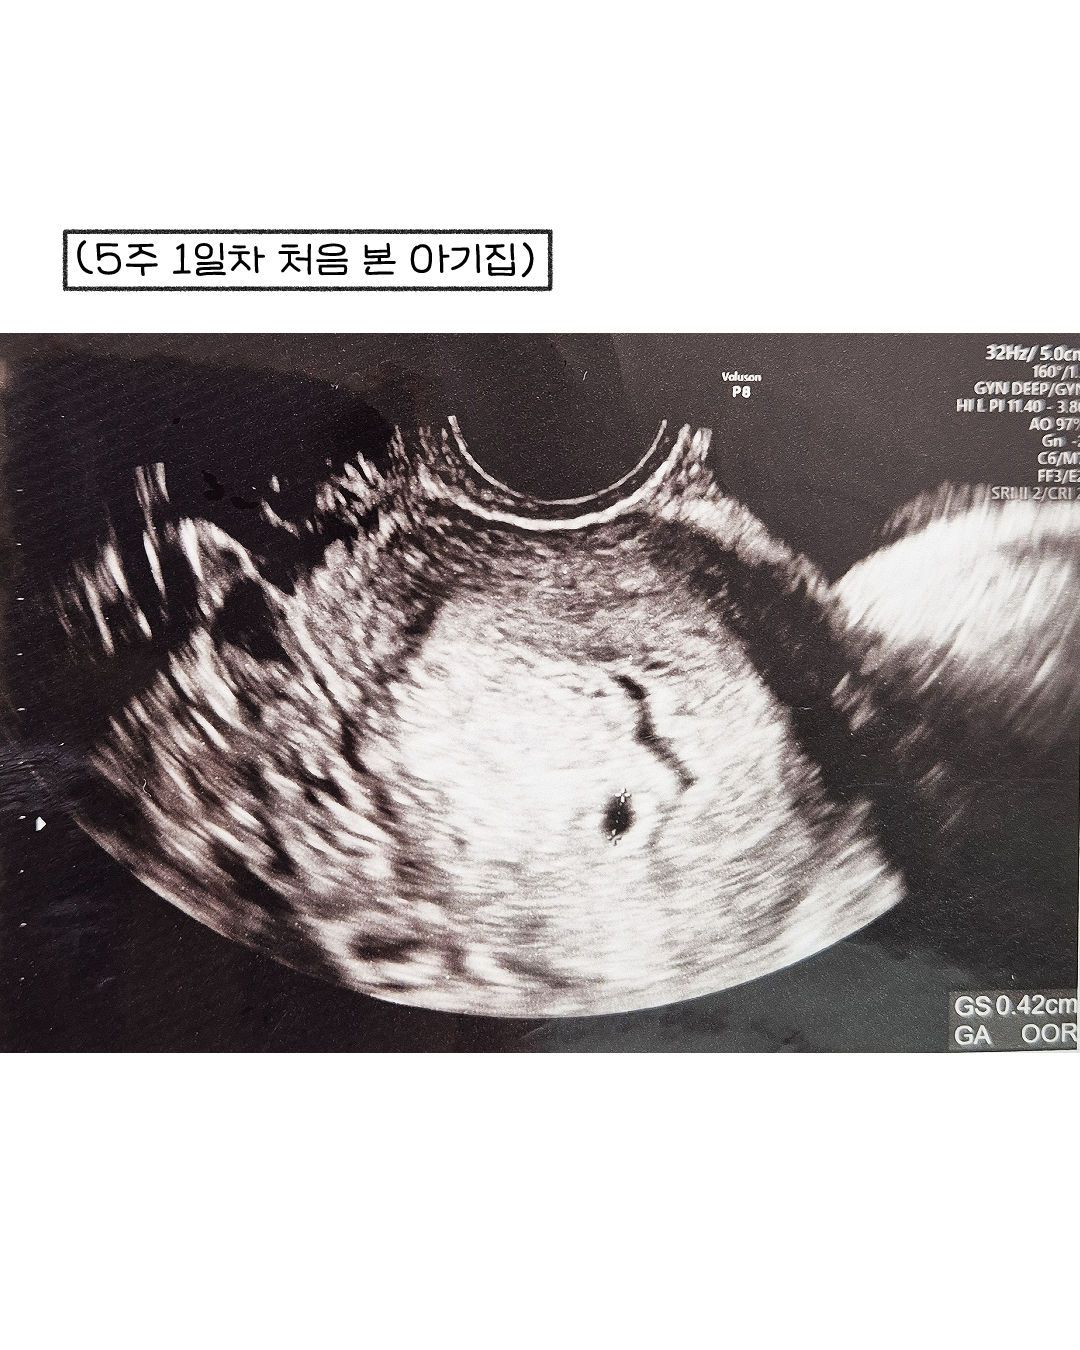

쉽지 않은 임신 초기.